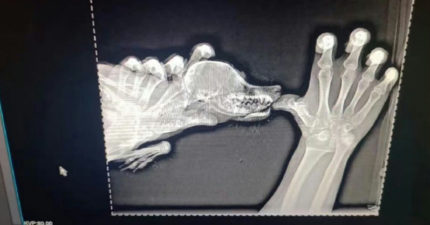

公園驚見「小鱷魚只剩下巴」上顎全消失 獸醫檢查後傻眼了